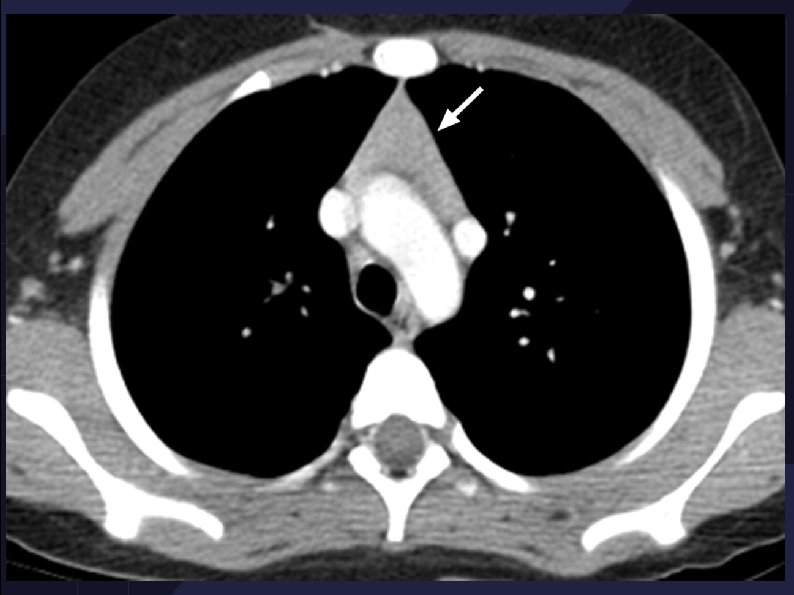

Thymic rebound hyperplasia in an 11 -year-old girl with Hodgkin lymphoma.